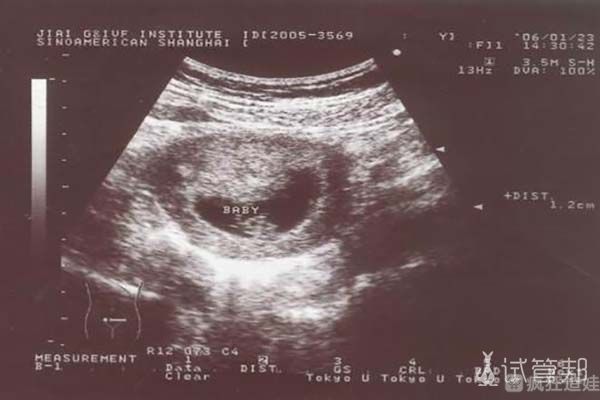

促排后就是等着取卵,取卵的结果还是挺不错的,受精成功6个,筛选后有3个可胚胎移植的。因为我们还是想要个男孩,就选择的男胚进行胚胎移植的。胚胎移植后我们就可以回去了,胚胎移植后的前三天还是要注意休息,尽量不要有很大的动作。当时每天都小心翼翼的,等到12天验孕的,孩子保住了。我是觉得好的医疗体系和服务真的让我在整个就医过程中都很顺利。